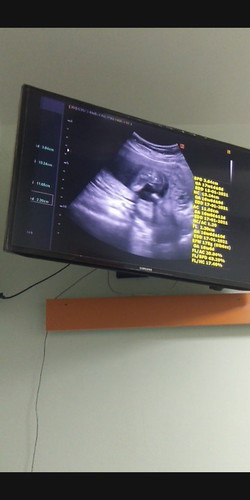

วันนี้ได้ 17w 2d. อยากรู้ว่าผู้ชายรึผู้หญิงคะ.